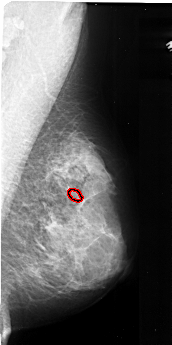

A_1037_1.RIGHT_CC

RIGHT_CC LINES 4411 PIXELS_PER_LINE 2416 BITS_PER_PIXEL 16 RESOLUTION 42 OVERLAY

FILE: A_1037_1.RIGHT_CC.OVERLAY

TOTAL_ABNORMALITIES 1

ABNORMALITY 1

LESION_TYPE CALCIFICATION TYPE PLEOMORPHIC DISTRIBUTION CLUSTERED

ASSESSMENT 4

SUBTLETY 1

PATHOLOGY MALIGNANT

TOTAL_OUTLINES 1

BOUNDARY